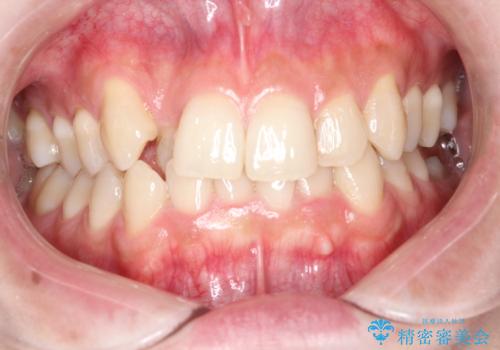

・切端咬合気味であった前歯の咬み合わせの関係

・前から2番目の歯がねじれており、部分的な反対咬合となっている

の改善を行いました。

写真ではわかりづらいですが、患者さんの希望により上下の歯をより内側に引くような動きを併行させています。